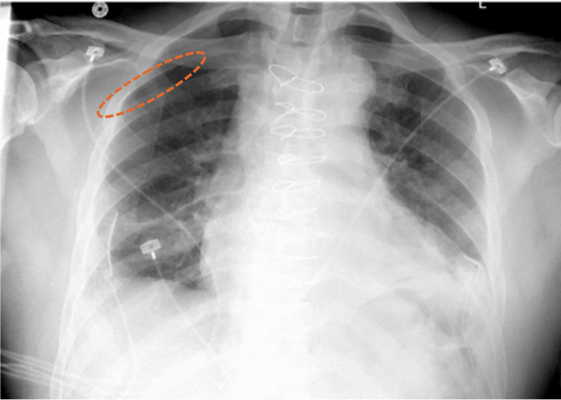

Aidoc’s newly FDA-cleared solution runs on all X-ray machines including portable ones, and is designed to analyze X-ray images. It automatically flags positive cases of pneumothorax, facilitating physicians to read X-rays in a timely manner.

The ability to quickly identify pneumothorax is imperative as it can worsen rapidly and result in respiratory or cardiac failure. This however is easier said than done, due to the extensive imaging volumes radiologists have to continuously examine. Aidoc’s highly accurate AI pneumothorax algorithm addresses this challenge by analyzing X-rays, flagging, and notifying physicians of the suspected findings.